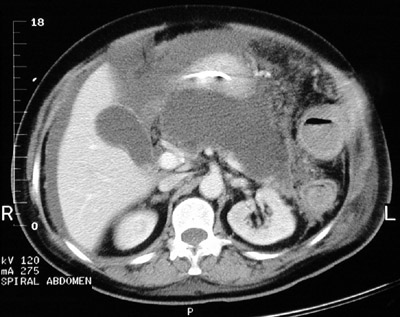

![]() | Here is a more florid example of acute pancreatitis seen in this abdominal CT scan. Note the large area of near fluid density in the region of the pancreas, representing marked necrosis that extends nearly to the gallbladder. There are surrounding peritoneal fluid collections as a result of the inflammation. |